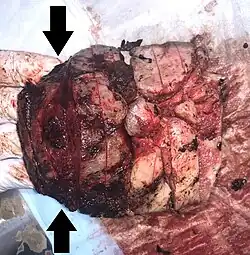

Gross pathology of severe intervillositis, with dark red and soggy tissue.